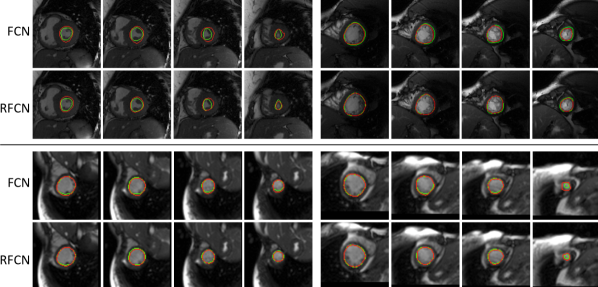

Refer to caption

Figure 3: Example of segmented left ventricle using RFCN and FCN architectures from MICCAI dataset (top two rows) [21] and PRETERM dataset (bottom two rows). Green contours represent the ground truth and red contours are the predicted contours. RFCN is often able to better delineate the left-ventricle contours with weaker boundaries compared to FCN.